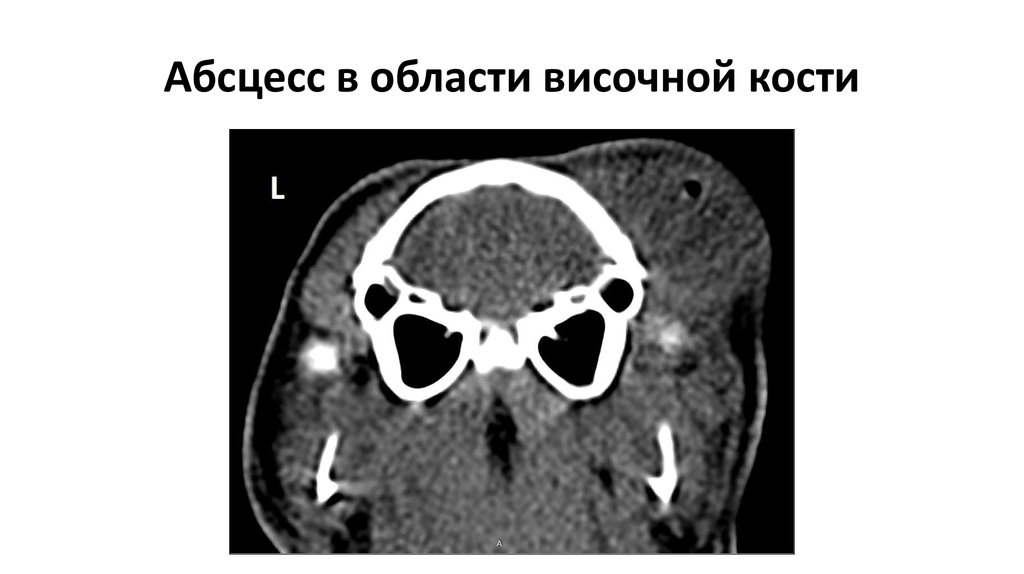

43.

Абсцесс в области височной кости